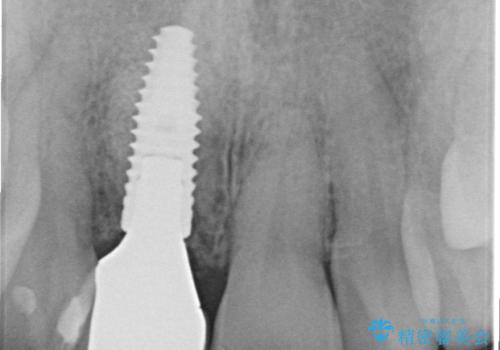

- 50万円(ストローマンインプラント・骨造成・ジルコニアカスタムアバットメント・ジルコニアクラウン)費用は治療当時の料金となります

前歯のインプラント治療は適切に行えば、ブリッジのように隣の歯を削らずに審美的で機能的な状態に仕上げることが可能です。

インプラント周囲に十分な骨や歯ぐきの厚みの整備を行うことで、審美的なインプラントの仕上がりを達成することができます。